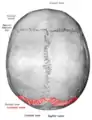

Skull seen from behind. Showing Λ-like shape of the lambdoid suture.

The lambdoid suture is between the paired parietal bones and the occipital bone of the skull. It runs from the asterion on each side.

The lambdoid suture is named due to its uppercase lambda-like shape.